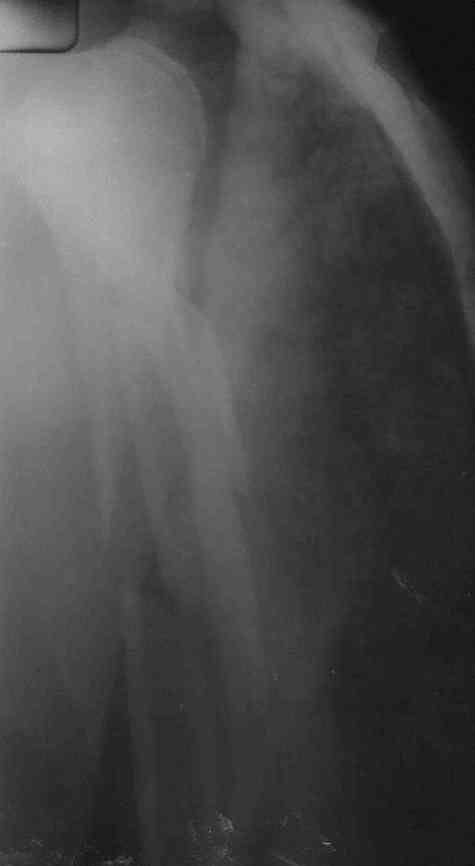

Немножко переделал повязку с отведением, подправил, вот что получилось.

Перелом внутрисуставной, Вы уверены на счет Сармиенто? На первичном снимке не видно было перелома головки.